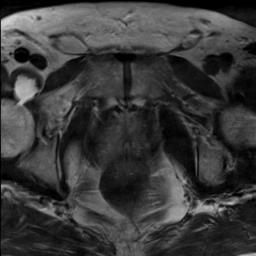

Modern deep neural networks struggle to transfer knowledge and generalize across diverse domains when deployed to real-world applications. Currently, domain generalization (DG) is introduced to learn a universal representation from multiple domains to improve the network generalization ability on unseen domains. However, previous DG methods only focus on the data-level consistency scheme without considering the synergistic regularization among different consistency schemes. In this paper, we present a novel Hierarchical Consistency framework for Domain Generalization (HCDG) by integrating Extrinsic Consistency and Intrinsic Consistency synergistically. Particularly, for the Extrinsic Consistency, we leverage the knowledge across multiple source domains to enforce data-level consistency. To better enhance such consistency, we design a novel Amplitude Gaussian-mixing strategy into Fourier-based data augmentation called DomainUp. For the Intrinsic Consistency, we perform task-level consistency for the same instance under the dual-task scenario. We evaluate the proposed HCDG framework on two medical image segmentation tasks, i.e., optic cup/disc segmentation on fundus images and prostate MRI segmentation. Extensive experimental results manifest the effectiveness and versatility of our HCDG framework.